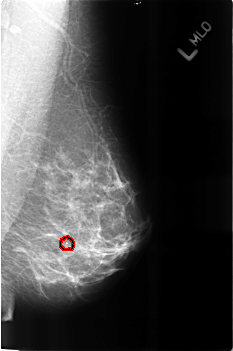

FILE: B_3160_1.LEFT_MLO.OVERLAY

TOTAL_ABNORMALITIES 1

ABNORMALITY 1

LESION_TYPE CALCIFICATION TYPE LUCENT_CENTERED DISTRIBUTION N/A

ASSESSMENT 2

SUBTLETY 4

PATHOLOGY BENIGN

TOTAL_OUTLINES 1

BOUNDARY